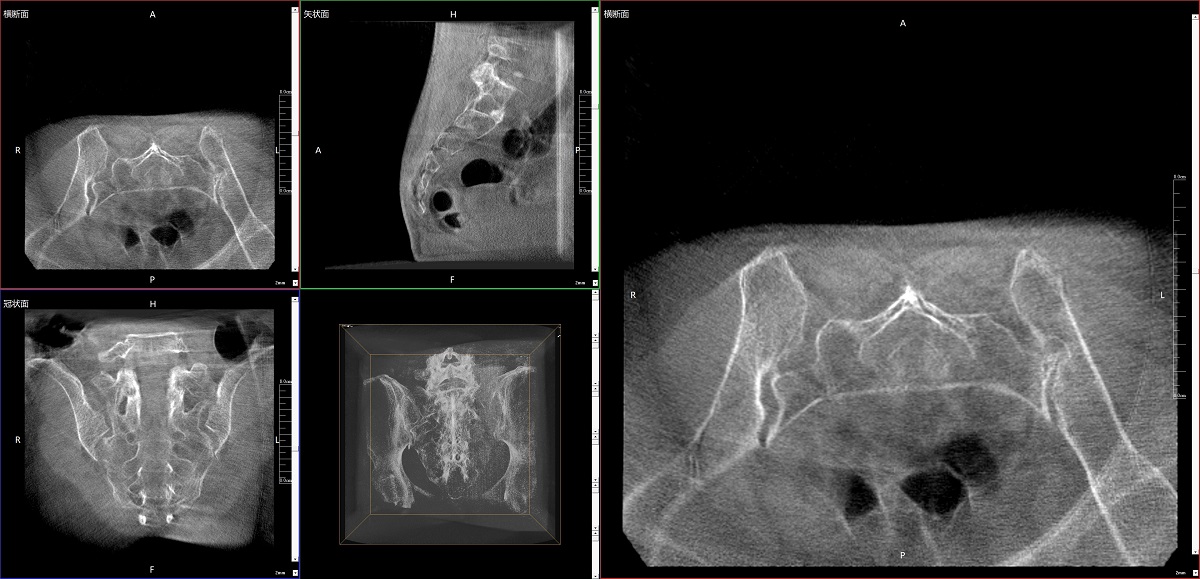

在骨科手術(shù)中,影像相當(dāng)于醫(yī)生的“眼睛”,要先“看得清",才能“算得準(zhǔn)” “打得穩(wěn)”。普愛(ài)醫(yī)療第三代平板三維C形臂協(xié)同醫(yī)院創(chuàng)傷導(dǎo)航機(jī)器人已開(kāi)展多例“骨盆骨折微創(chuàng)手術(shù)”,成為上海市第七人民醫(yī)院手術(shù)技術(shù)創(chuàng)新的一大亮點(diǎn)。

普愛(ài)醫(yī)療第三代平板三維C形臂出色的二維透視和術(shù)中三維成像效果,為機(jī)器人提供了精確的術(shù)中影像依據(jù),協(xié)同提升手術(shù)整體的精準(zhǔn)度和效率,為患者帶來(lái)了更安全、更高效的醫(yī)療服務(wù)體驗(yàn)。